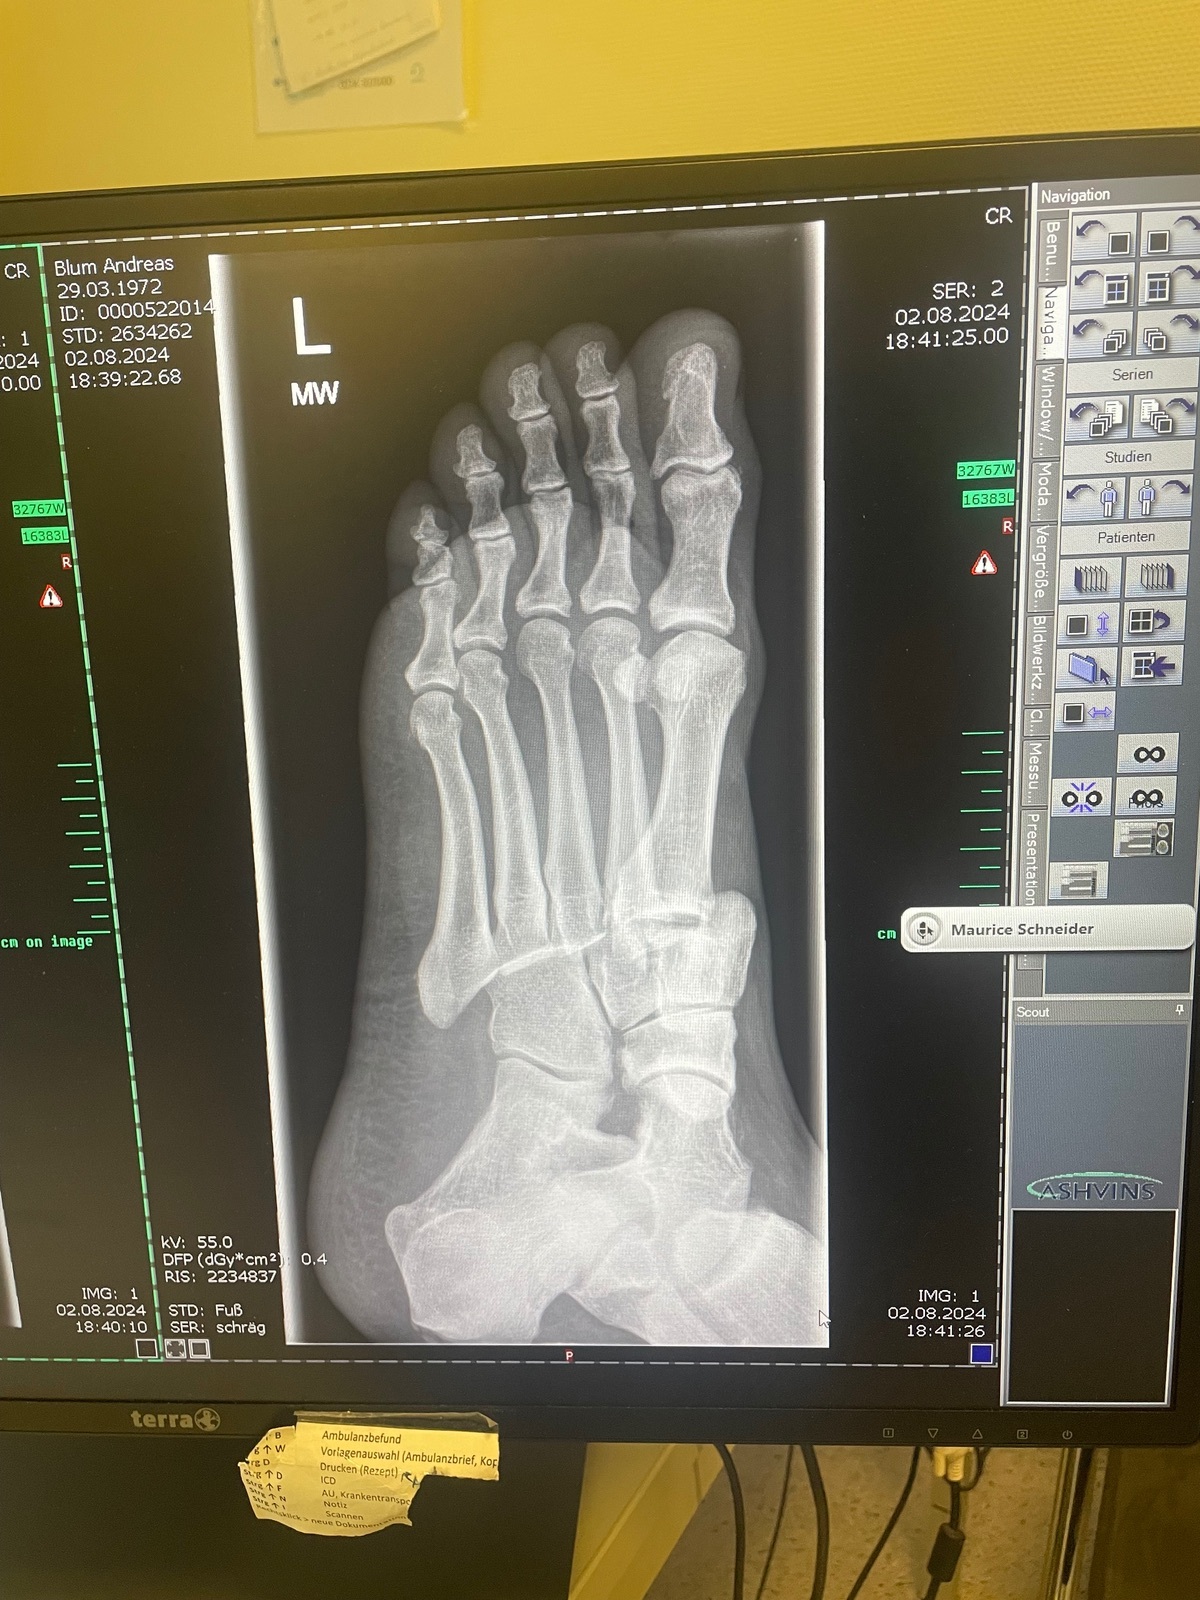

Offensichtlich traf meine Fußraste oder ein anderes hervorstehendes Teil meinen Vorderfuß und klemmte den ein. Die Folge: alle Mittelfußknochen wurden aus der Position gedrückt und etwa „eine Zehe“ weiter nach links verschoben.

Die Sache nimmt mich für diese Saison aus dem Rennen und wird mich sicher 4-5 Monate beschäftigen, drei davon, ohne dass ich den Fuß belasten darf, anschließend Physio.